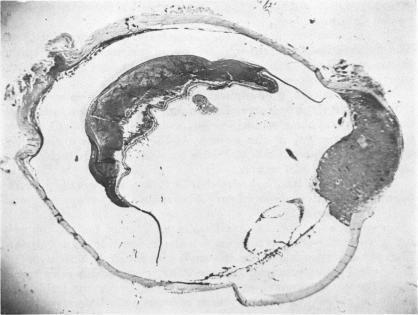

Intraocular biopsy: an evaluation.

Trans Am Ophthalmol Soc. 1952;50:375-405.